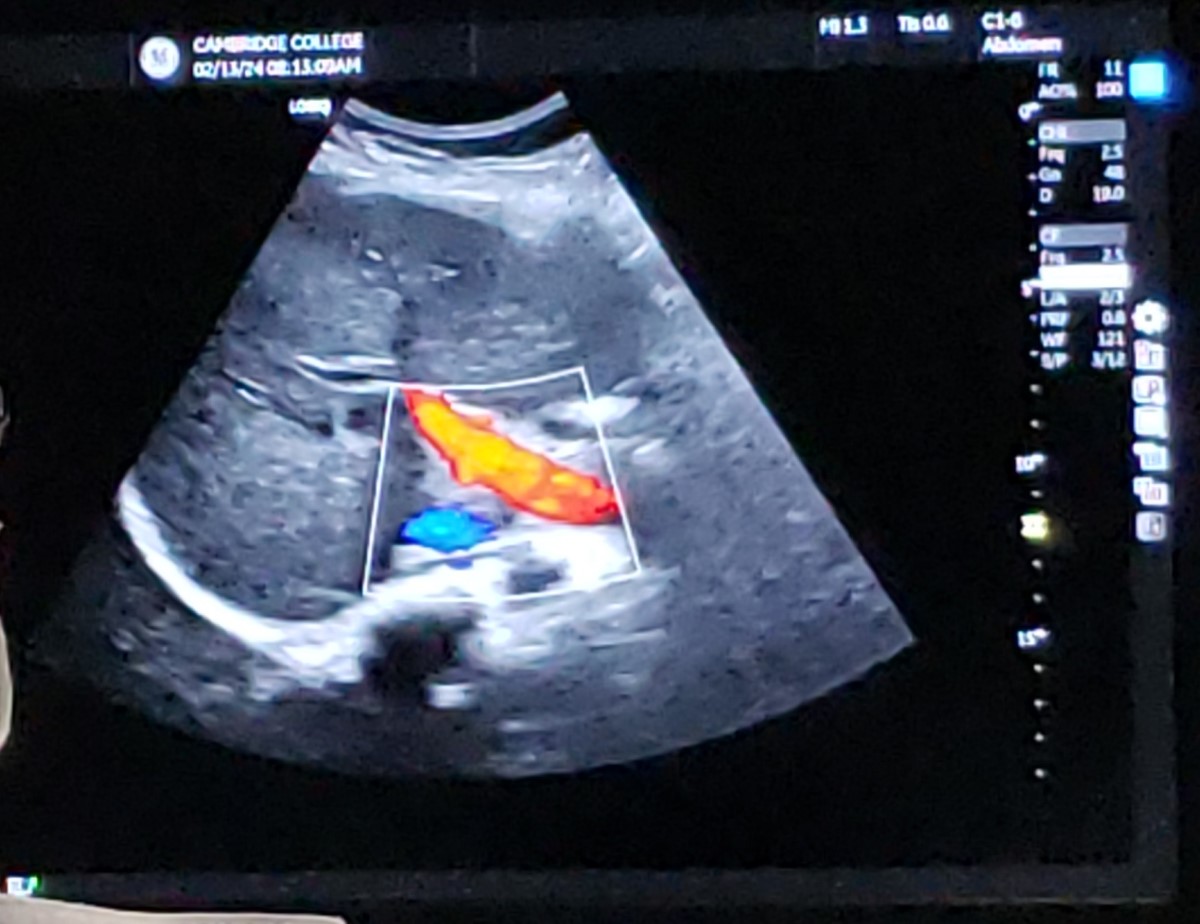

New cards

Trans RLL w/ MPV - color